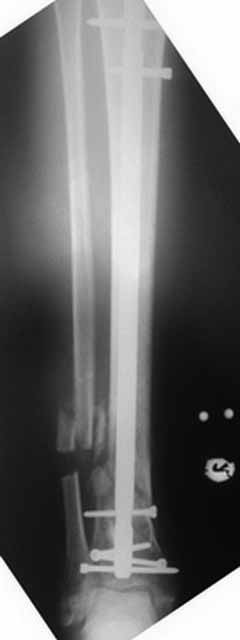

Как-то вот нет уже желания открываться в зоне ложного сустава. Мы бы

попытались сделать закрыто. Винт в дистальном отломке удалить через прокол.

Кусок гвоздя оставить. Новый гвоздь (солидный), возможно с покрытием.

Примерная ситуация. Пациент 37 лет. Синтезировали где-то пластинкой. Попал к нам через 2 месяца.

19 апреля убрали через проколы пластину с винтами, пересекли fibula, наложили аппарат.

Немного потянули по оси, убрали вальгус, ротацию. 22 апреля (на 3-е сутки) заштифтовали окончательно. 29 апреля выписали из отделения. На все ушло 10 дней.

С уважением, Никита Заднепровский